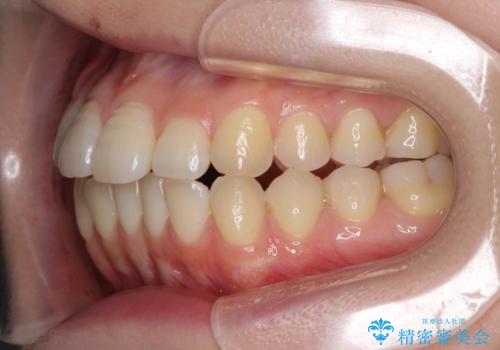

オープンバイトのインビザラインを用いた再矯正

- 矯正治療の後戻りを気にして来院された患者様です。

オープンバイト(前歯の開咬)と下顎骨の偏位による不正咬合が認められました。

骨格の偏位による不正咬合は改善しきれないことを理解いただいた上で、インビザラインにて矯正治療を行うこととしました。

オープンバイトは後戻りを起こしやすいため、極力そのリスクを軽減するため、奥歯を圧下させるように治療を進めていきました。

下顎骨の偏位が顕著であったため、上下の正中を合わせることはできませんでしたが、患者様には大変満足していただきました。